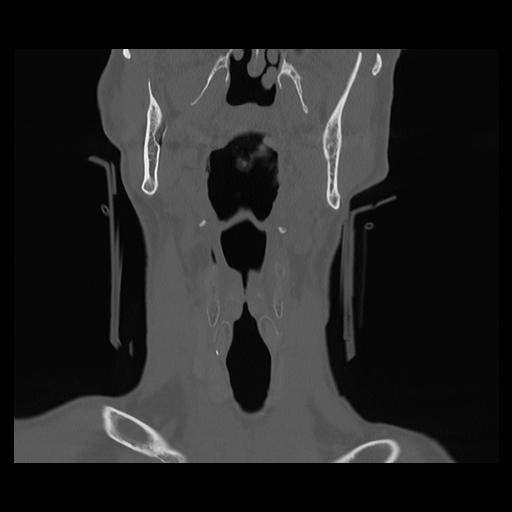

16 HUESO,,Coronal,2.000,HUESO,Coronal,